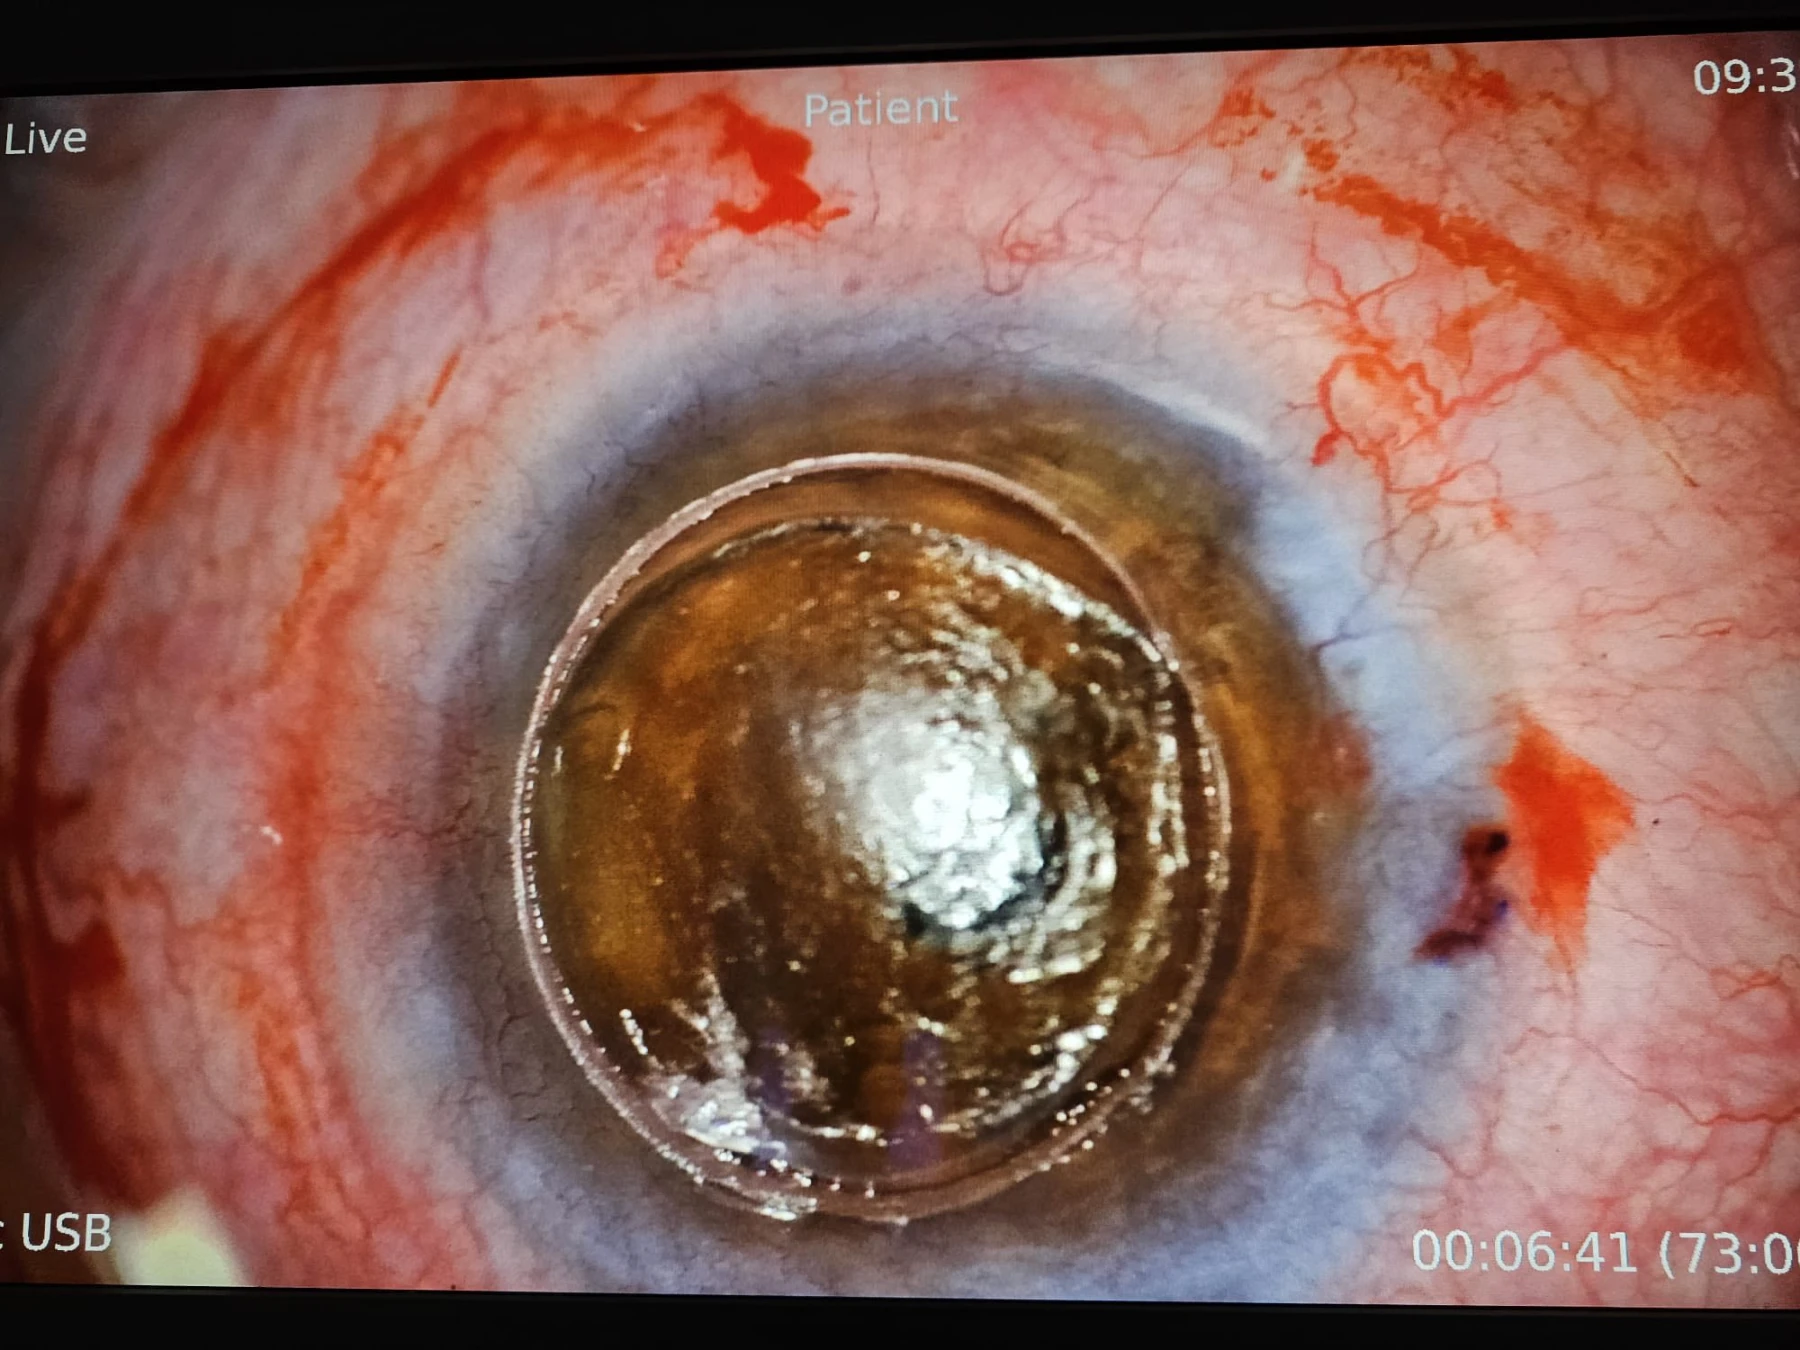

Keratoconusul este una dintre cele mai frecvent întâlnite distrofii corneene, constând în deformarea neregulată și progresivă a corneei, care ia o formă de con, cu subțiere extremă în vîrful lui, pînă la complicația de “spargere” a acestei zone foarte subțiate, urmată de hidrops cu perforație sau / și de cicatrici fibroase în vârful acestui con. În stadiile lui cele mai avansate, când vederea pacientului este foarte scăzută, singurul tratament este operația de transplant de cornee, iar tehnica de elecție este transplantul lamelar anterior DALK, deoarece, prin acesta, se păstrează endoteliul cornean propriu al pacientului, endoteliul fiind stratul cel mai “valoros” al corneei, dar și cel răspunzător pentru 90% din situațiile de respingere a grefonului – de aceea, dacă se poate păstra, merită păstrat!

Iar când pacientul este foarte tânăr (17 ani în cazul de azi) și boala e avansată la ambii ochi, tânărul neputând să se descurce singur, nu doar că operația se impune cât mai repede, dar e de dorit să fie un transplant lamelar anterior DALK sau unul perforant “Mushroom”, cu păstrarea unei suprafețe cât mai mari din endoteliul propriu pacientului.

Tehnologia femtolaser este de mare folos în ambele tehnici menționate. Mai jos, cîteva secvențe din operația efectuată de dr. Cristian Moraru.